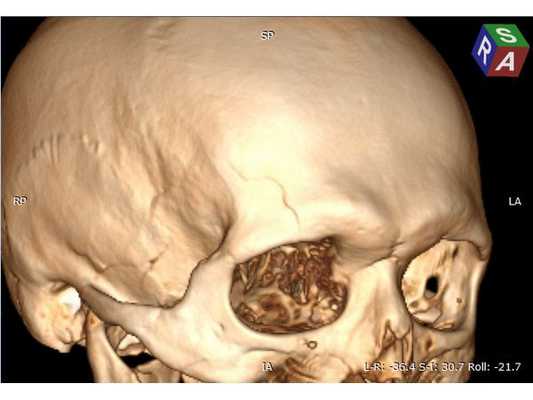

В связи с отрицательной динамикой неврологического статуса и рентгенологической картины принято решение об оперативном вмешательстве: 1. Удаление внутримозговой гематомы через фрезевое отверстие; 2. Нижняя трахеостомия (для проведения длительной искусственной вентиляции лёшких). Техническая сложность заключалась в широких лобных пазухах пациента, т. к. фрезевое отверстие весьма желательно было наложить, не вскрывая лобную пазуху, но в то же время непосредственно в проекции внутримозговой гематомы. Для этого выполнена предоперационная разметка проекции внутримозговой гематомы на свод черепа. Операция №1 (длительность — 25 минут): ⠀• выполнен 4 см линейный разрез мягких тканей в лобной области справа параллельно естественным морщинам; ⠀• скелетирована кость, произведён гемостаз электрокоагуляцией по ходу доступа, визуализирован линейный перелом лобной кости; ⠀• с помощью краниотома наложено фрезевое отверстие и гемостаз воском; ⠀• твёрдая мозговая оболочка вскрыта крестообразо, визуализирован выход внутримозговой гематомы на кору головного мозга; ⠀• путём аспирации и отмывания физиологическим раствором удалена внутримозговая гематома общим объёмом около 30 мл; ⠀• произведён гемостаз перекисью водорода, дефект твёрдой мозговой оболочки укрыт материалом Surgicell, костная стружка уложена во фрезевое отверстие; Операция №2 (длительность — 15 минут): ⠀• выполнен 3 см линейный вертикальный разрез мягких тканей в проекции трахеи; ⠀• тупым и острым путём обнажена передняя поверхность трахеи и взята на крючок; ⠀• П-образно рассечены два полукольца и заведена трахеостомическая трубка №8.5; ⠀• наложены швы на мягкие ткани, трахеостомическая трубка подшита к коже, наложена асептическая повязка. Всё оперативное вмешательство вместе с анестезиологическим пособием уложилось в 1 час, выполнено с минимальной кровопотерей.

Представленный пример может быть рассмотрен как вариант хирургической тактики при агрессивных очагах ушиба головного мозга. Так, при минимальной хирургической агрессии решены основные проблемы: за один наркоз удалена внутримозговая гематома и выполнена трахеостомия, позволившая освободить полость рта для дальнейшей работы челюстно-лицевого хирурга и проведения продлённой искусственной вентиляции лёгких. Предоперационная 3D-разметка позволила рассчитать доступ — непосредственно в проекции внутримозговой гематомы, но без вскрытия лобной пазухи. Стоит отметить, что удаление травматической внутримозговой гематомы через фрезевое отверстие технически вполне выполнимо, хотя, конечно, обзор весьма ограничен.